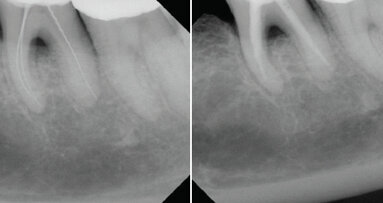

Komplexní klinická studie ukázala, že endodontické léčebné protokoly zahrnující nástroje Reciproc (Dentsply Sirona) podporují lepší léčebné...